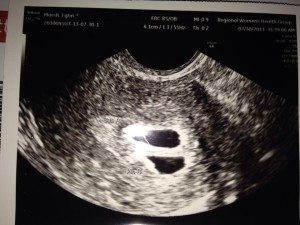

I thought I was having a miscarriage due to some bleeding. We went to get checked at my doctor (I was 9 weeks). I prayed the whole way and couldn’t look at the screen when she did the ultrasound. She asked my husband, “Do you see what I see?” He sighed and smiled and said, “A baby…” She said, “I see 2…” I told my husband I prayed so hard God gave us another one! Emotions went from one extreme to the other…

We found out our previous pregnancy wasn’t viable at our 8 week ultrasound. So going into this ultrasound (also at 8 weeks), so soon after, I was completely detached. And he was scared. So we got on the table and she started. She goes, “Ah, there’s the heartbeat. And here’s the other one.” And my husband just went, “The other what?” She replies, “Heartbeat.” And he still didn’t catch on. I turned my head and said, “There are 2 babies.” And then it went crazy from there. They are 15 months now.

I was 6 weeks pregnant and spotting. It was my first pregnancy and I thought I was having a miscarriage. We went for an ultrasound and not only was everything fine but it was twins! Such an emotional roller coaster of a day! We were definitely excited and my husband was spacing out all day — I’d have to wave my hand in front of his face to get his attention, LOL!